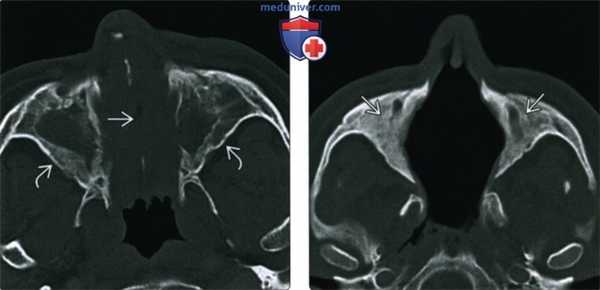

(Слева) На аксиальной КТ в костном окне полость носа полностью заполнена мягкими тканями, пневматизация обеих верхнечелюстных пазух тотально снижена. Определяется перфорация носовой перегородки утолщение и склероз стенок пазух - все изменения сопоставимы с ГПА.

(Справа) На аксиальной КТ в костном окне у пациента с поздней аадией ГПА определяется деструкция костных структур полости носа, в т.ч. носовой перегородки. Верхнечелюстные пазухи облитерированы вследствие утолщения костной ткани.

• КТ в костном окне:

о Часто наблюдается перфорация носовой перегородки

о Точечные очаги деминерализации кости:

- По ходу перфорирующих артерий; признак васкулита

о Деструкция носовых раковин и наружной стенки полости носа (крючковидного отростка и внутренней стенки верхнечелюстной пазухи):

- Вначале разрушаются перегородка и раковины, затем обе верхнечелюстные пазухи, после чего-остальные пазухи